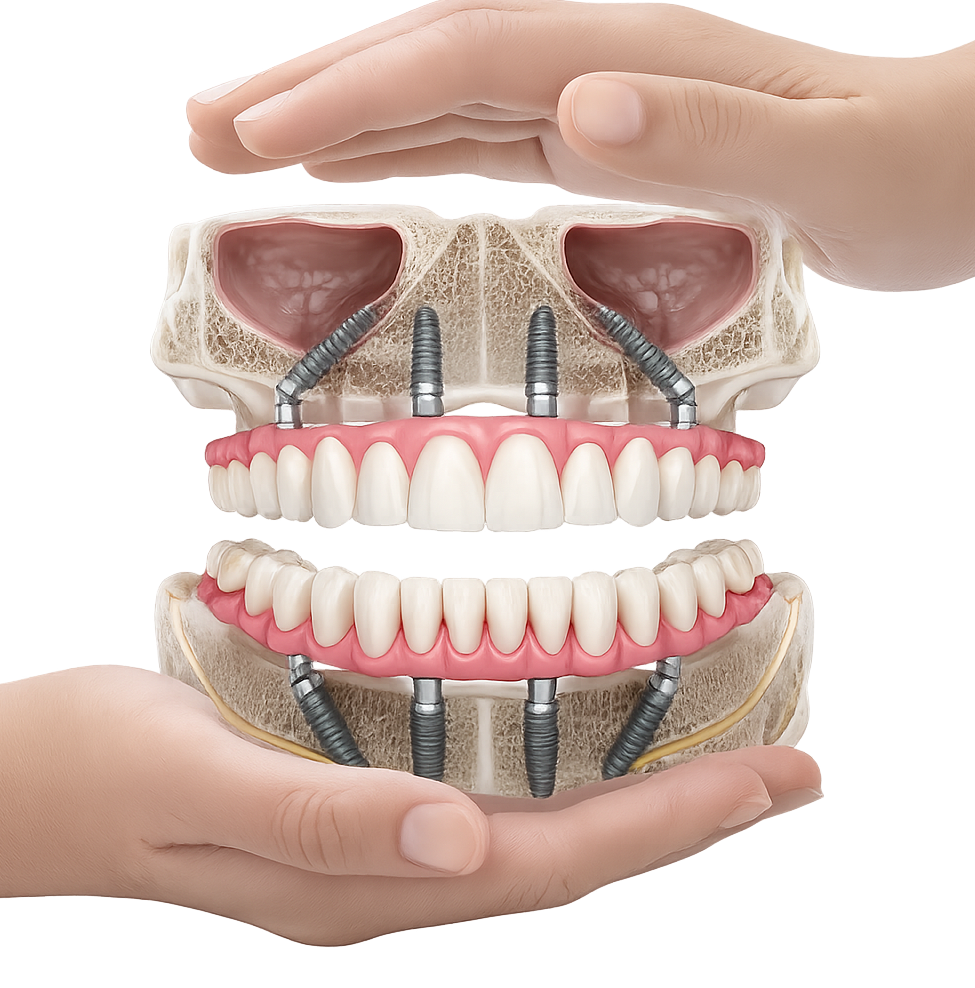

anul 1998, dr. Paulo Malo a introdus pentru prima dată conceptul All-on-4 în reabilitarea orală a pacienților, obținând rezultate remarcabile. De atunci, mii de pacienți au beneficiat cu succes de această tehnică. Sistemul de implanturi utilizat inițial în acest concept a fost Nobel Biocare, o companie cu o vastă experiență și o bază solidă de pacienți tratați, susținută prin numeroase

studii științifice.În cazurile de atrofie osoasă severă, când inserarea implanturilor în zonele laterale nu este posibilă fără adăugare osoasă, conceptul All-on-4 prevede plasarea implanturilor în unghiuri strategice pentru a evita zonele deficitare. Astfel, două implanturi sunt plasate în zona incisivilor laterali, iar alte două în zona premolarilor.

Pentru pacienții cu edentație extinsă sau dinți nefuncționali, conceptele All-on-4 și All-on-6 oferă soluții fixe, moderne și eficiente, care asigură estetică, confort și funcționalitate superioară față de proteza mobilă.